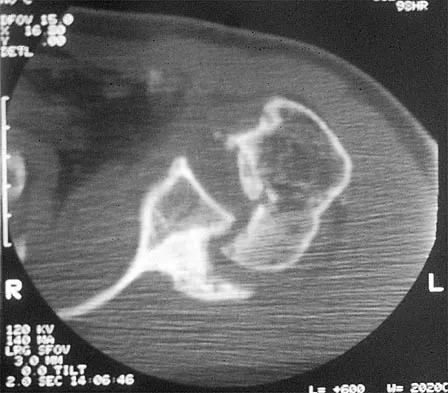

The oblique radiograph of the foot and the CT scan shown in Figures 10a and 10b show a patient whose symptoms have failed to respond to rest and non-steroidal anti-inflammatory drugs. What is the best course of action?

Explanation